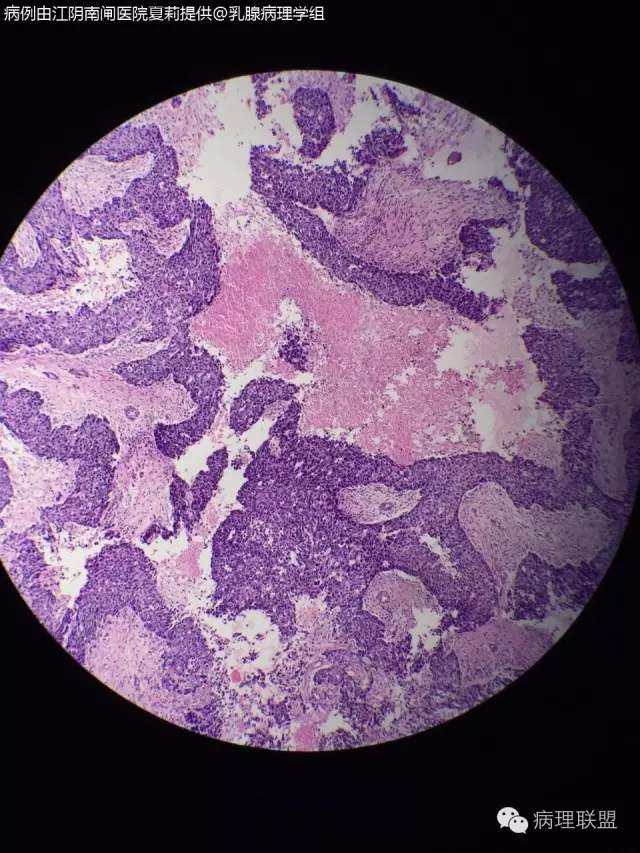

43岁女性,右乳肿物发现一个月入院,b超:低回声结节(2.2*1.3cm),双侧乳腺腺体增生。临床未考虑恶性。大体:灰白色不整形肿物,2.5*2cm大小,切面有一2*1.5大小的圆形区域,实性,质软,周围似有包膜。(病例由江阴南闸医院 夏莉 提供,致谢!)

浸润性导管癌

我考虑髓样癌,但我没见过髓样癌的片子,依据的是一些书上的关于髓样癌的描述。请各位老师指教

高级别导管癌的异形性也可以很像髓样癌的心态,好像还有腺管样结构。导管癌还是放第一位。

感觉髓样癌不是很够,有部分特征可以发具有部分髓样癌特征的浸润性导

现在新版也没有髓样癌的这个术语了,就叫伴有髓样癌特征的浸润性导管癌